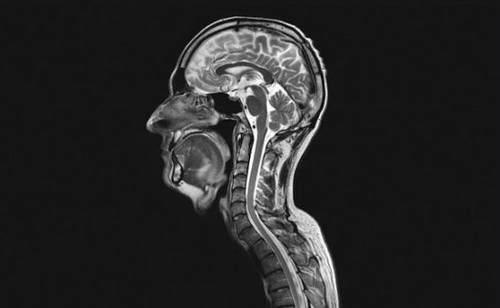

5、核磁共振成像( MRI )

在核磁共振成像仪器下,患者躺在圆柱形磁体内,暴露于强大的磁场。一旦暴露在磁场中,水分子的质子会排成一行,要是遭到无线电波的攻击,它们会立即乱作一团,不成直线。在质子重新排列过程中,电脑会收集它们的信号,并加工成图像。富含水的组织会发出更强烈的信号,在生成的图像中看上去更亮,而骨骼相对较暗。这项技术用在此处是来描述大脑和颈部动脉的。在注射了用于对比的成像剂以后,放射线专家重复扫描,这时,成像剂在血管中移动,使他们可以看清楚造成中风、脑动脉瘤和各种外伤的堵塞物。

脊椎管和大脑处的明亮区域表示脑脊髓液

核磁共振成像技术还经常用在神经成像方面。脊椎管和大脑处的明亮区域表示脑脊髓液;向下延伸至身体的长条状体则是脊髓。